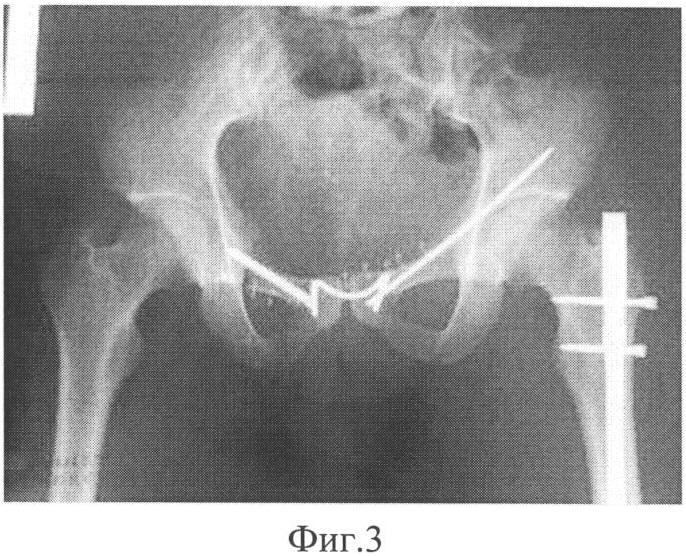

Фиг.4. Рентгенограмма таза через один год после операции (а – прямая проекция, б – каудальная проекция).

Больной В., 25 лет, история болезни 3710, госпитализирован на 1-е сутки после получения травмы с диагнозом: Сочетанная травма. Сотрясение головного мозга. Перелом лонной и седалищной костей таза слева. Перелом седалищной кости таза справа. Разрыв лонного сочленения. Перелом дна и задней стенки левой вертлужной впадины. Поперечный перелом средней трети левой бедренной кости. Внутрисуставной оскольчатый перелом медиального мыщелка левой большеберцовой кости. Продольный оскольчатый перелом левой лучевой кости (фиг.2). На четвертые сутки больному произведена операция: металлодез лонного сочленения в надлобковой области. Произведен разрез до 5 см, выделено место разрыва, затем при помощи сверла сформировались отверстия в области бугорков лонных костей, идущие косо вниз и кнутри под углом до 20°. После охлаждения скобы с металлопамятью формы и сведения лонных костей до полного контакта внедряют бранши скобы в заранее приготовленные отверстия. При температуре тела скоба возвращается в изначальную форму, тем самым удерживая лонное сочленение (фиг.3). Остеосинтез передней колонны вертлужной впадины слева спицей с нарезкой, остеосинтез лонной кости блокируемым винтом, интрамедуллярный остеосинтез левой бедренной кости. Послеоперационный период протекал без особенностей. Больной активизирован на 1-е сутки в пределах кровати, а на 2-е сутки поставлен на костыли. Функция восстановлена полностью. Больной осмотрен через один год после оперативного вмешательства (фиг.4). Жалоб нет, укорочений нижних конечностей нет, ходит без средств дополнительной опоры, полный безболезненный объем движений в тазобедренных суставах, нарушений со стороны сексуальной функции не отмечено. На рентгенограммах – взаимоотношения суставных поверхностей в лонном сочленении хорошие, отмечается консолидация переломов.